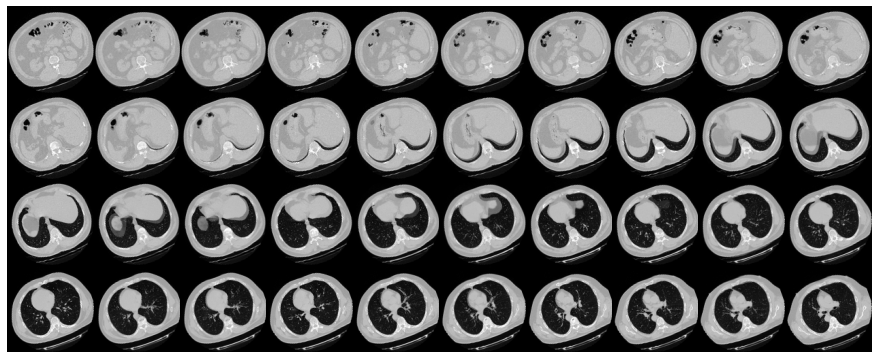

数据包含 3 种胸部癌症类型,即腺癌、大细胞癌、鳞状细胞癌和 1 个正常细胞文件夹 数据文件夹